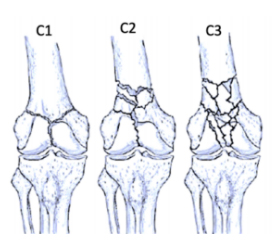

AO/OTA Classification

• Type C: Complete articular fractures

ao-classification-distal-femur-type-c